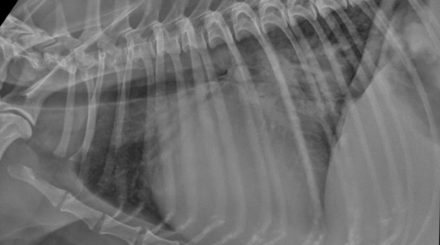

Radiography Reading ‘Thoracic Imaging’ (28/01/2025)

Our radiography reading sessions are a great way for our Specialists to bring new and interesting diagnostic imaging conundrums for discussion with our vtx community. In this session, the theme…